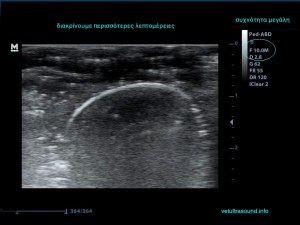

3) Τη συχνότητα, δηλαδή όσο πιο μεγάλη είναι αυτή, τόσο πιο πολλές λεπτομέρειες βλέπουμε αλλά ταυτόχρονα αυξάνονται τα τεχνουργήματα από αέρα και άλλες δομές. Οι αρμονικές βοηθούν στην καταστολή αυτών των τεχνουργημάτων.